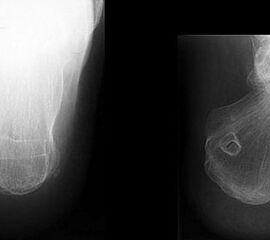

Knöcherne Ausrisse lassen sich in der seitlichen Röntgenaufnahme des Sprunggelenkes ausschließen oder beweisen (Abb. 5). Eine Sonderform bilden hier die Entenschnabelfrakturen des Kalkaneus.

Abbildung 5